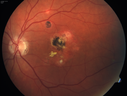

Serpiginouse Choroiditis (Chorioretinitis) - Acute Right Eye - Old Left Eye VA 20/25 OD , 20/50 OS822 views63-year-old woman has serpiginous choroiditis (date - March 2011). The right eye has not been previously involved, and then she noticed new onset floaters in the right eye for the last two weeks. Her vision in the right eye is hazy because of that.

VISUAL ACUITY: Vision OD is 20/25, OS is 20/50